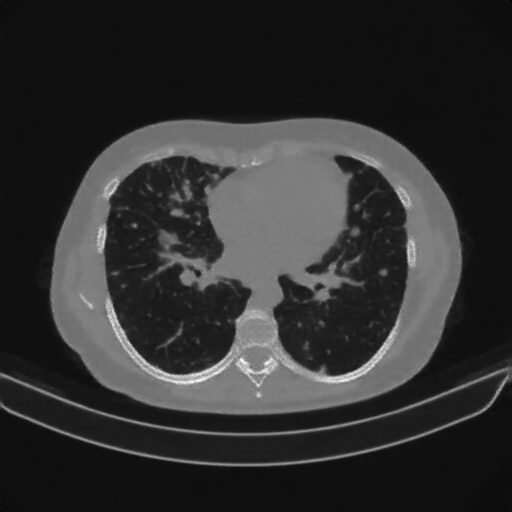

Targeted Slice 70 - Lung Window Analysis (Generated vs Real Venous)

0.728

Lung SSIM

109.0

Lung RMSE

48.5

Lung MAE

Average Lung Window Metrics Across All Slices (133 slices) - Generated vs Real Venous

0.727

Lung SSIM (Avg)

108.6

Lung RMSE (Avg)

46.1

Lung MAE (Avg)

Generated VENOUS CT scan (A→B translation)

Lung window (WL -600, WW 1500 β†’ Low βˆ’1350, High +150)